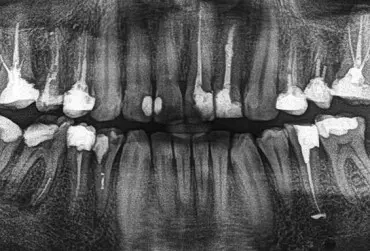

By-pass złamanego narzędzia – opis przypadku

W artukule przedstawiono proces leczenia pacjenta, u którego podczas próby leczenia kanałowego doszło do odseparowania fragmentu narzędzia endodontycznego. Zastosowano technikę by-pass w celu udrożnienia kanału oraz dalsze procedury endodontyczne.